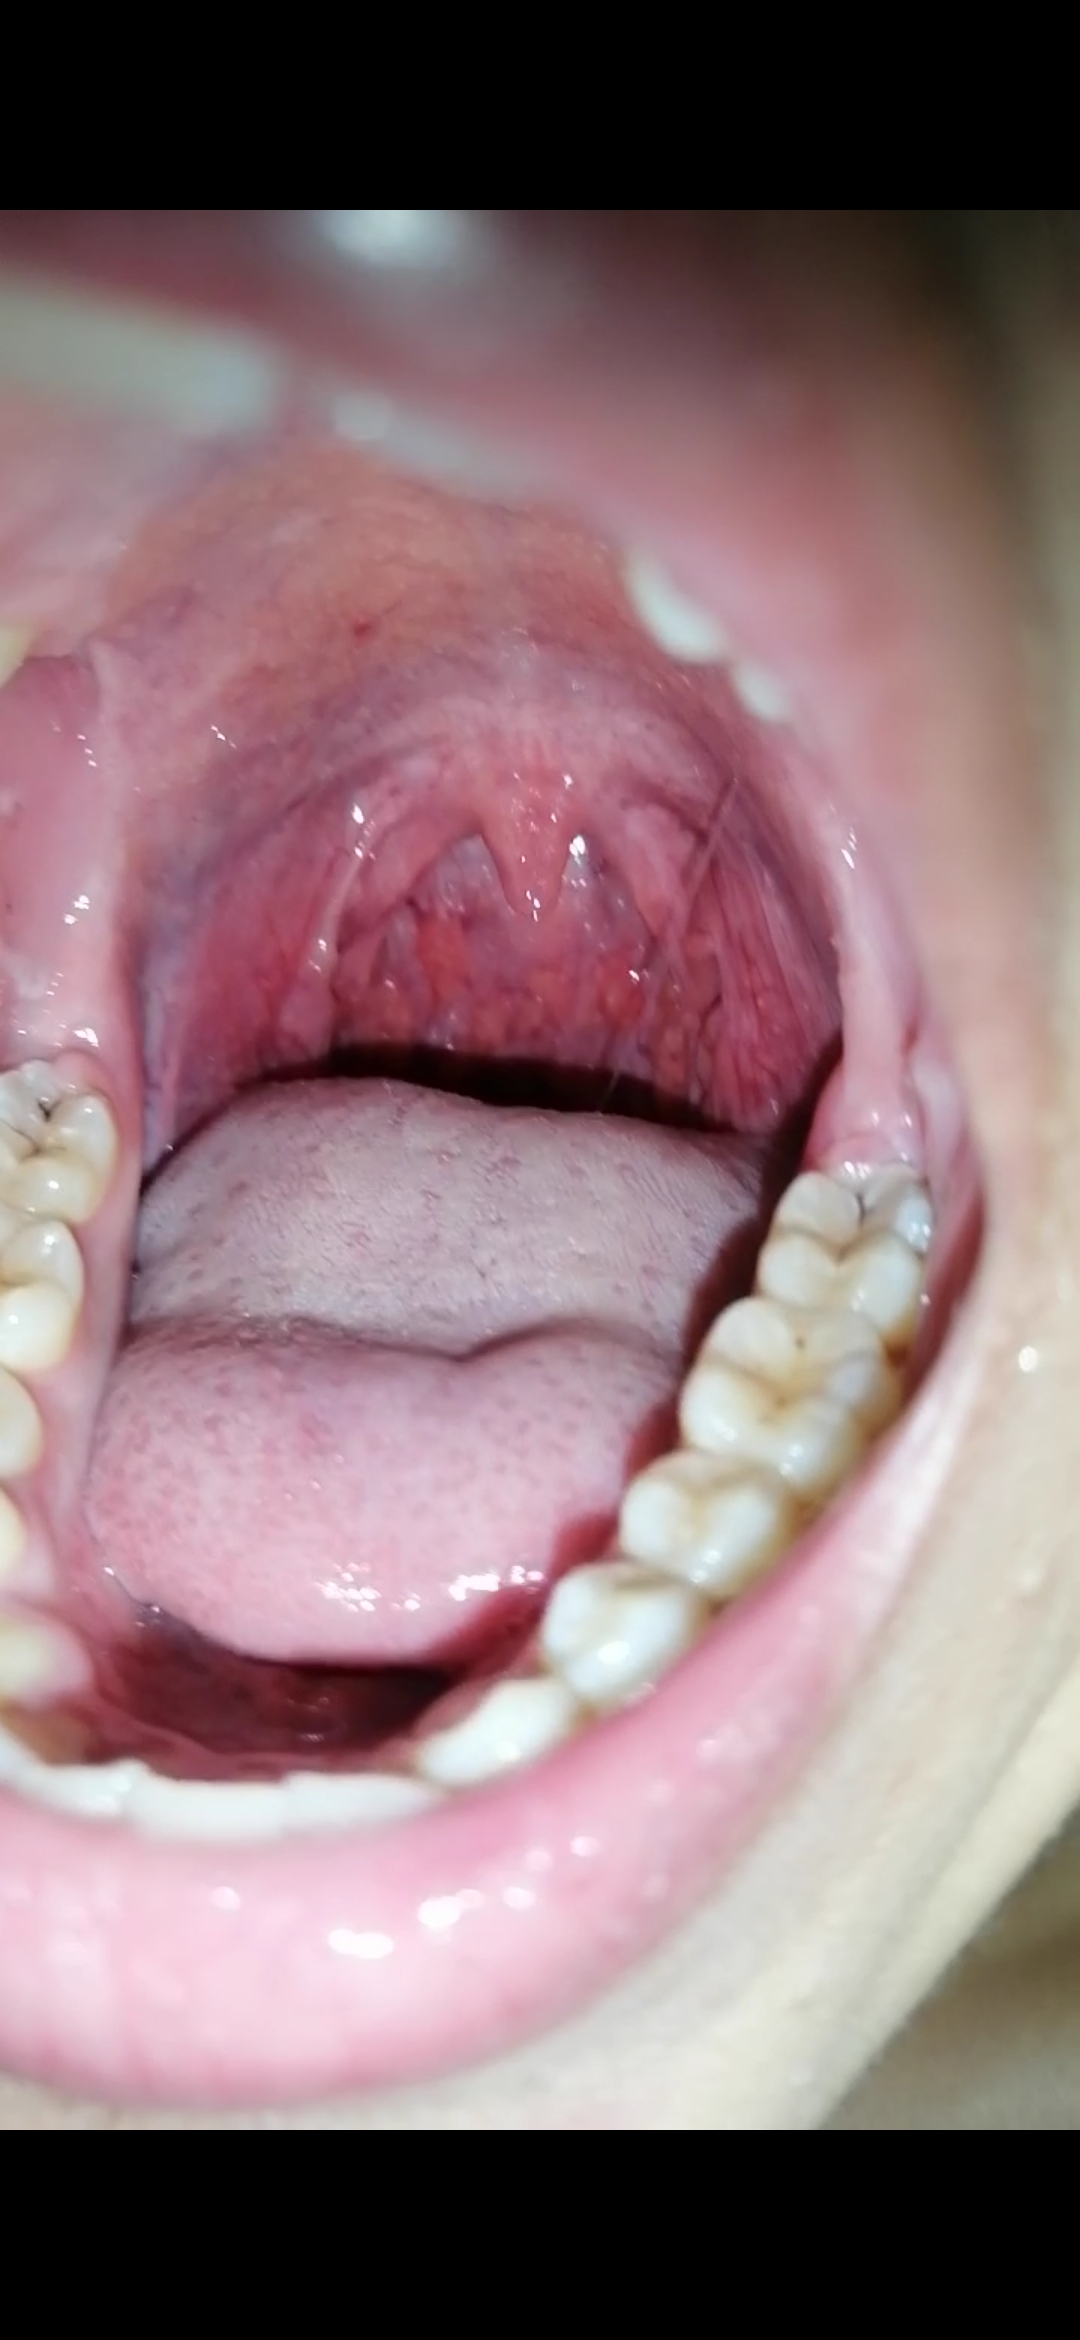

Hola asesor Enrique M ...comenze a salir con un chico y ya después tuvimos relaciones, a los días me salieron como bultos en mi garganta amarillentos con bolas rojas en la lengua con tos y gripe, fui al medico me vio la garganta pero no me dijo nada, tengo 17 necesito saber si podría ser VIH, alguna ETS o otra infección menor